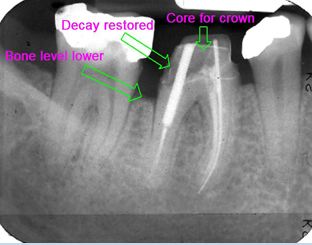

Routine restorative crown lengthening is a surgical procedure that judiciously reduces the gum tissue and often the underlying bone surrounding one or more teeth so that an adequate amount of healthy tooth surface is available for the restorative dentist to properly restore a damaged tooth. Damaged teeth are often too short to be covered in a manner that will provide good support and predictable retention of a new crown or other restoration. Failure to prepare the tooth properly will often set up a situation that will either fail prematurely or force a patient to deal with compromised comfort or esthetics. These crown lengthening procedures are designed to remove small amounts of gum tissue and bone around the damaged portions of the tooth without significantly reducing the strength or stability of the teeth in the same region. The site that requires this treatment is usually allowed to heal and the tissue to mature for a time-frame of four to six weeks before your dentist can start the final repair process that will ultimately save your tooth.